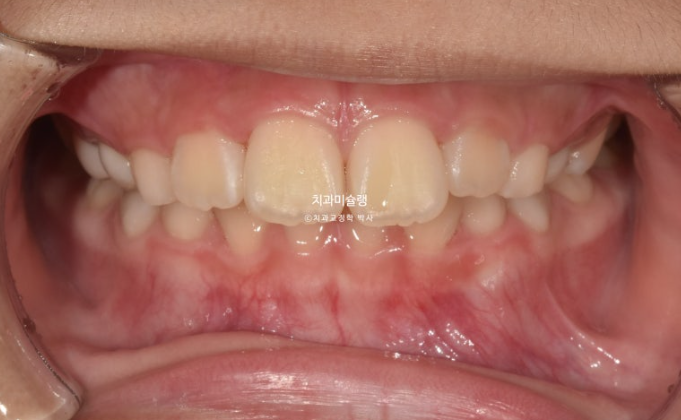

23년 10월 압구정 어린이 교정

교정치료를 위해 온 어린이 입니다.

23.10

윗니가 아랫니를 많이 덮어 아래 앞니가 안 보이는 과개교합이 있습니다.

중심선 불일치도 보입니다.

윗니 뻗침이 있어서 돌출을 느끼는 상태입니다.

앞니 위아래 4개씩 총 8개 영구치 앞니는 약간의 삐뚤함이 있지만 큰 공간부족 없이 잘 나온 편 입니다.